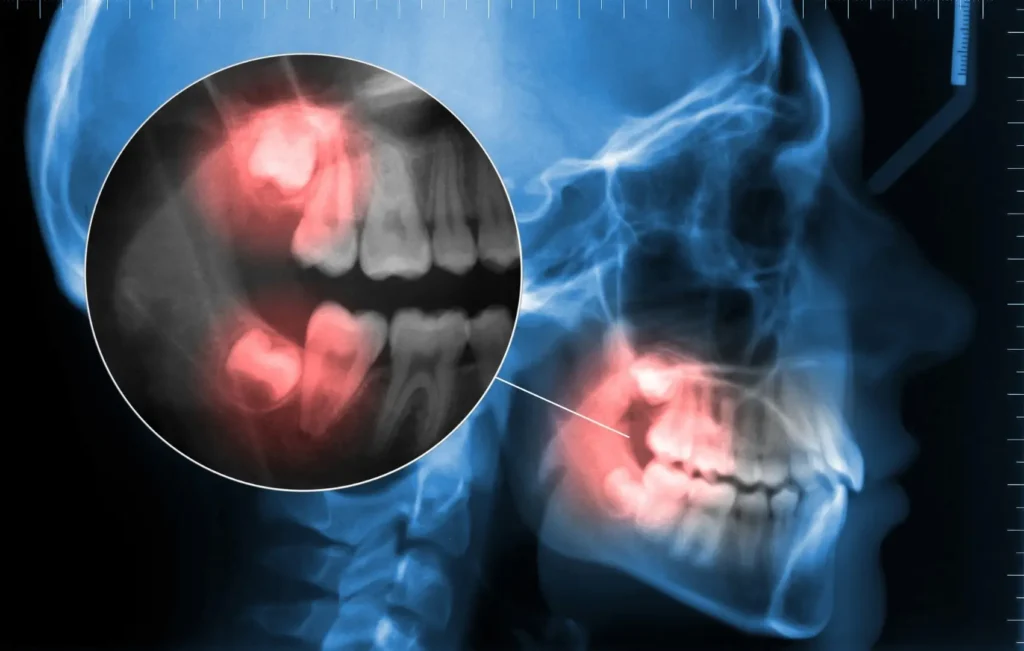

Cysts and Bone Loss: Impacted teeth can form cysts, risking damage to jawbone and nerves.

X ray highlighting an impacted lower wisdom tooth in red

We begin with a detailed exam and CBCT or panoramic X-ray to locate roots, evaluate nerve proximity, and plan a safe removal.